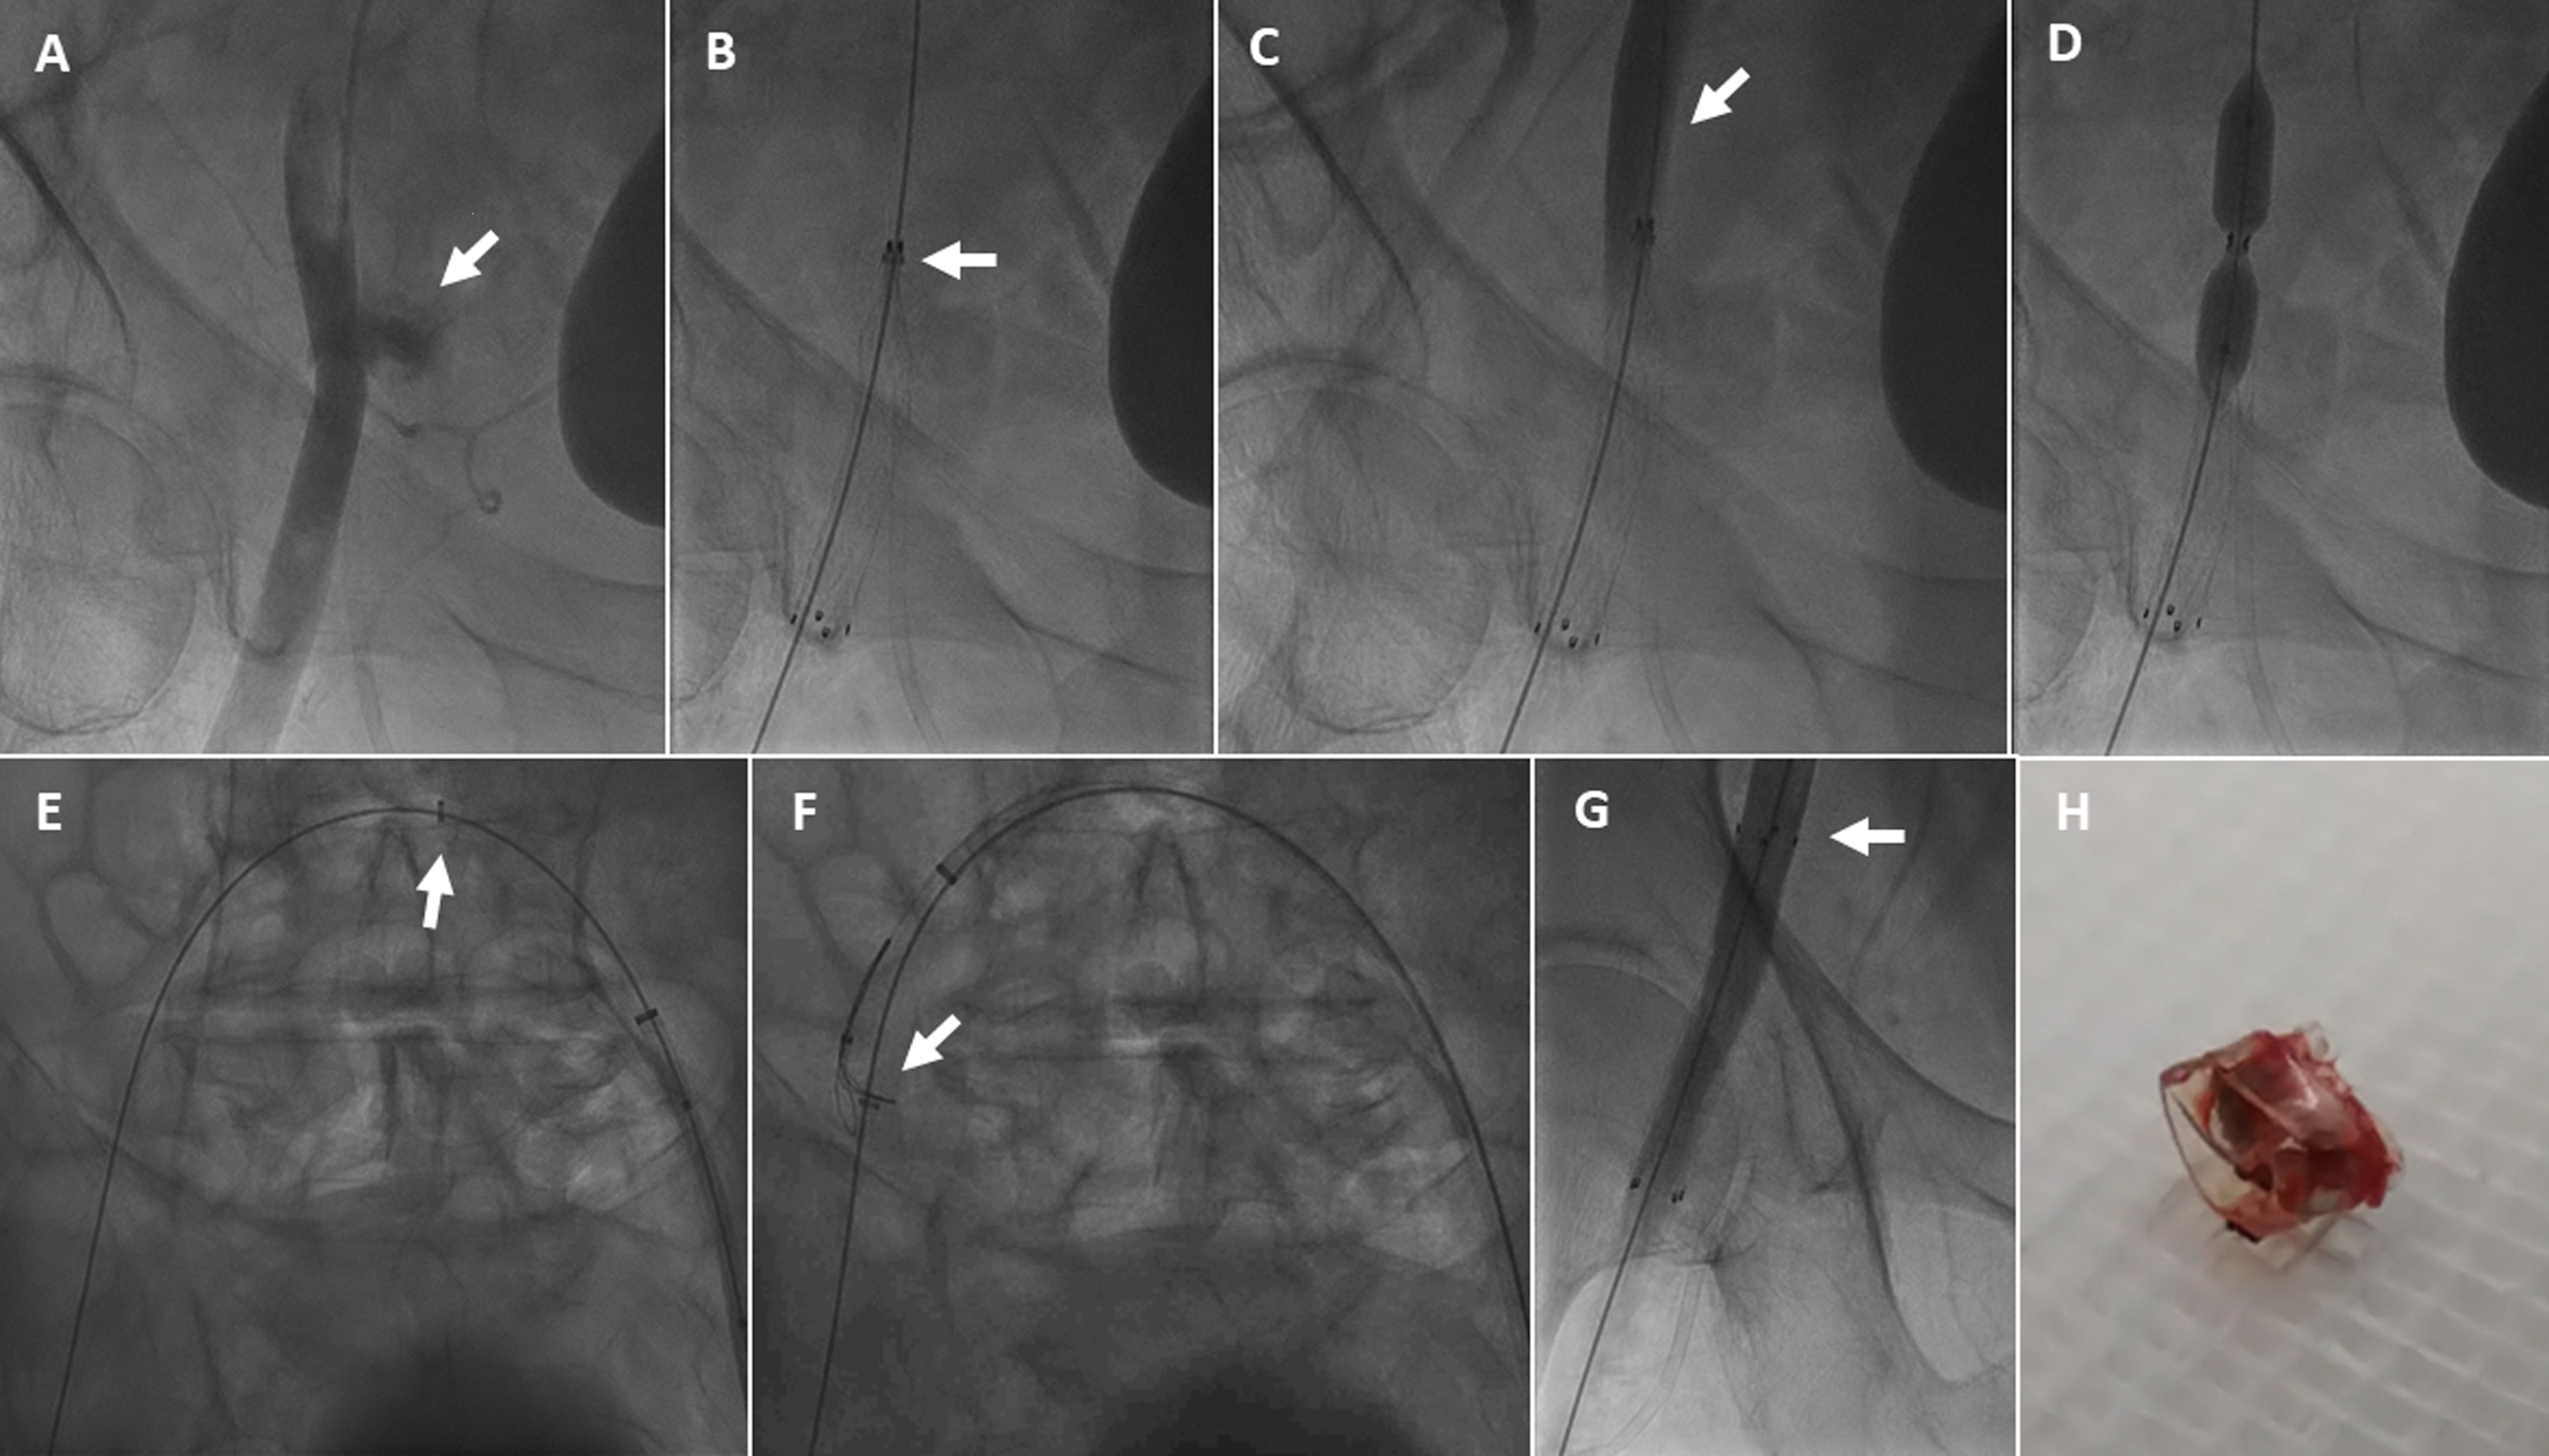

A 69-year-old diabetic man with morbid obesity underwent elective angioplasty for a chronic total occlusion of the left anterior descending coronary artery via right radial (7F) and right femoral (8F) access. Following successful stenting, the right common femoral artery (CFA) was closed using a Perclose ProStyle device (Abbott). The patient became hypotensive, and angiography via radial access revealed bleeding at the right CFA as a result of ProStyle failure (Figure A).

A 10F Flexor Check-Flo sheath (Cook Medical) was advanced via the contralateral left CFA. A 12 × 60-mm Fluency Plus Endovascular Stent Graft (BD) was deployed to seal the perforation in the right CFA. During deployment, a radiopaque ring-like component remained attached to the proximal edge of the stent graft, preventing expansion (Figure B( and leading to arterial occlusion (Figure C). Balloon angioplasty with a 10.0 × 40-mm POWERFLEX Pro balloon (Cordis) failed to expand the stent or displace the ring (Figure D). After balloon deflation and withdrawal, the ring migrated proximally over the guidewire (Figure E, Video 1), allowing proximal expansion of the stent graft. Retrieval attempts using a 4.0 × 40-mm Mustang balloon (Boston Scientific) were unsuccessful. The ring was ultimately captured and retrieved using a 12 x 20-mm EN Snare Endovascular System (Merit Medical) (Figure F, Video 2). Final angiography confirmed complete stent-graft expansion and restored blood flow (Figure G, Video 3). The left CFA was successfully closed with a Perclose ProStyle device.

We describe a previously undescribed complication: incomplete deployment of a stent graft, leading to vascular occlusion. Although the source of the detached component could not be confirmed (Figure H), its radiopacity and morphology suggest it was part of the delivery system. Prompt percutaneous retrieval using balloon and snare techniques resolved this complication without need for vascular surgery.